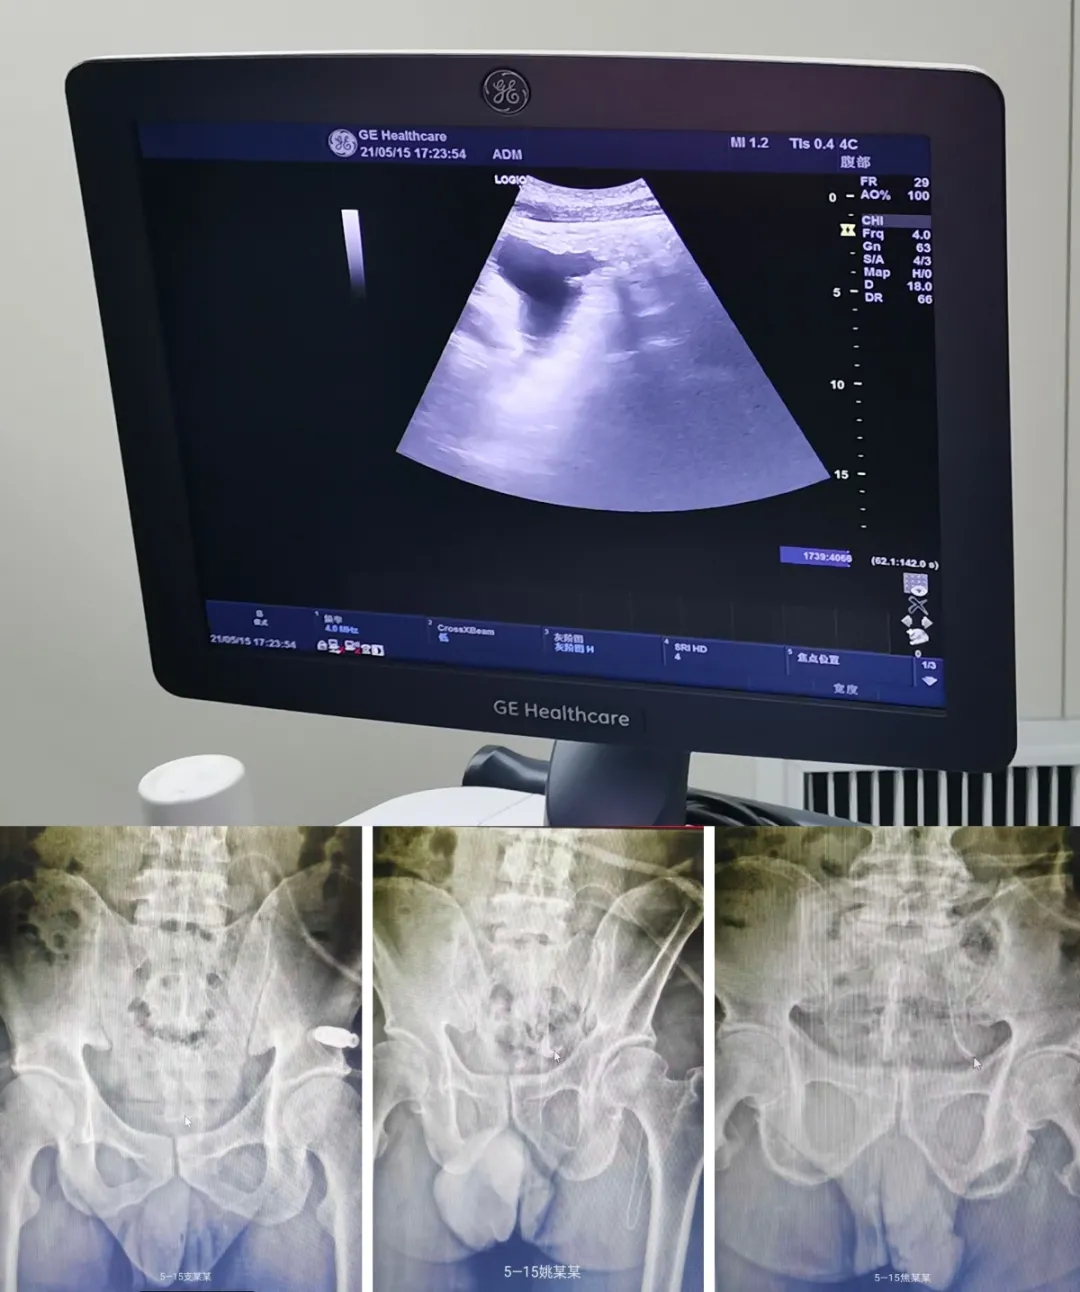

我院成功开展运城市首例彩超引导下经皮穿刺腹膜透析置管术

近日,我院血液透析科在哈尔滨医科大学第二医院孔凡武教授指导下完成了运城市首家彩超引导下经皮穿刺腹膜透析置管术共 3 例。经评估患者支某某、姚某某、焦某某均适合该置管方式,3 名患者先后在彩超引导下成功完成腹膜透析置管。术中彩超及术后DR片均提示腹透导管末端到达理想位置,出入液体顺畅。

彩超引导下经皮穿刺腹膜透析置管术,术中实时彩超引导,避免位置不当,判断导管末端位置,以便及时调整,具有导管生存率高、手术时间短、操作简单,无荷包缝合、局麻、创伤小、住院时间短等优点。此次置管成功,标志着我科腹膜透析置管术达到国内先进水平。